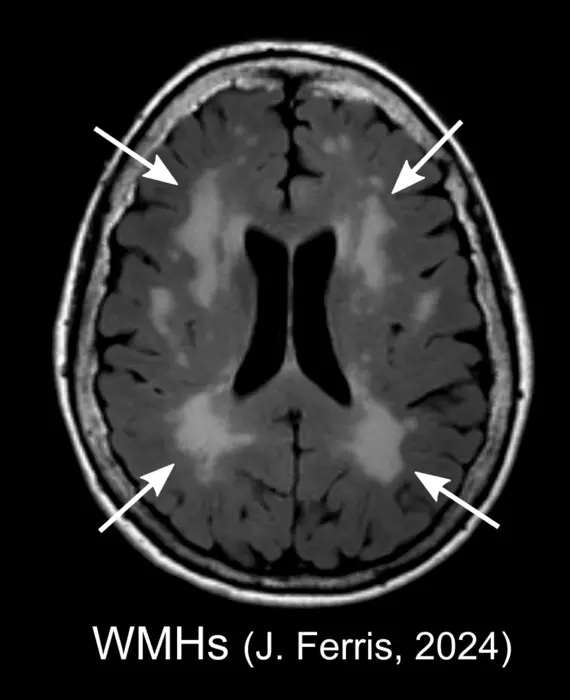

Spots on an MRI White Matter Hyperintensities

white matter hyperintensities [IMAGE] EurekAlert! Science News Releases Why Is White Matter White The white matter on the other hand primarily consists of myelinated axons and the supportive glial cells. It contains three major groups of axons: It contains nerve fibers (axons), which are extensions of nerve. Association fibers, commissural fibers, and projection fibers. White matter, which is made up of countless thin strands that act like communication cables, is mostly found deep. Why Is White Matter White.